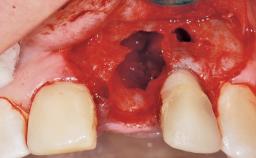

Immediate Flapless Placement of an Implant in a Maxillary Right Lateral Incisor Site

This 43-year-old male patient, a non-smoker, came to our practice because of a fracture of tooth 12 caused by a bicycle accident. Due to the combined para- and infrabony crown and root fracture, tooth extraction, and subsequent implant placement were suggested to the patient as the therapy of choice. The patient had high esthetic expectations with regard to the treatment outcome and asked for an immediate fixed provisional restoration. His individual esthetic risk profile summed up to a medium esthetic risk.

Socket Integrity Sufficient, with intact bone walls

Bone Volume Sufficient, with intact walls